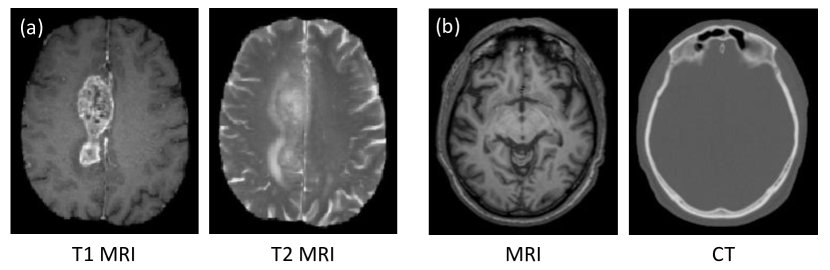

Many researchers have tried to directly synthesize high-quality demanded medical modality images [6, 15]. However, it is quite challenging due to the following possible problems. Firstly, the mapping from the source modality to the target modality (or its inverse) is typically complex and ill-posed [7]. Moreover, different modalities may show quite different image appearances, e.g., MRI and CT as shown in Fig. 1(b). Furthermore, certain regions in the image have totally different image contrast and even different shapes, for instance, the tumor regions in Fig. 1(a). Despite all these challenges, there are potential connections between the two modalities if we observe deep enough. That is, the mapping from source modality to target modality should be highly non-linear so that it can bridge the significant appearance gap between the two modalities.

Refer to caption

Figure 1: Three pairs of corresponding source (left) and target (right) images from the same subjects. (a) shows a pair of T1 MRI/T2 MRI brain tumor images; (b) shows a pair of MRI/CT brain images.